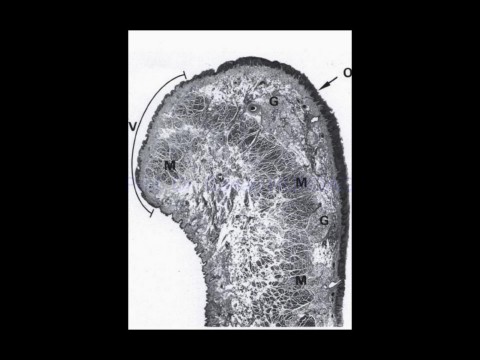

20-Apr-20                                         Üst Sindirim Sistemi,                                                    22